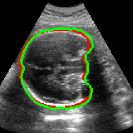

As mentioned in Sec. 3.2, it is crucial for our brain extraction network to work consistently regardless of the orientation of the brain within the US volume. This can be qualitatively observed in Fig. 3, which shows the outline of the brain-extraction prediction and the corresponding ground-truth, in red and green respectively, for six different 3D US volumes. These volumes have been selected to demonstrate the amount of variation between each scan, with the position of the fetus inside the mother as well as the position of the brain in respect to the scan varying drastically from case to case.

As shown in Fig. 3 , the network’s prediction is remarkably close to the ground-truth, regardless of the position of the brain in the volume. It also manages to accurately predict the location of the brain when this is partially obscured either by the cropping or the shape of the ultrasound beam.